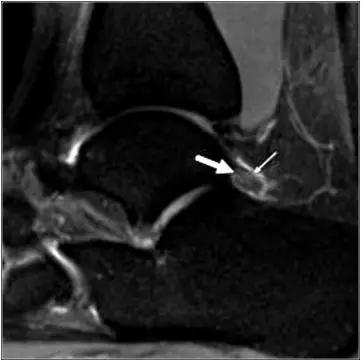

T1WI FS C+

异常增厚的前胫腓韧带